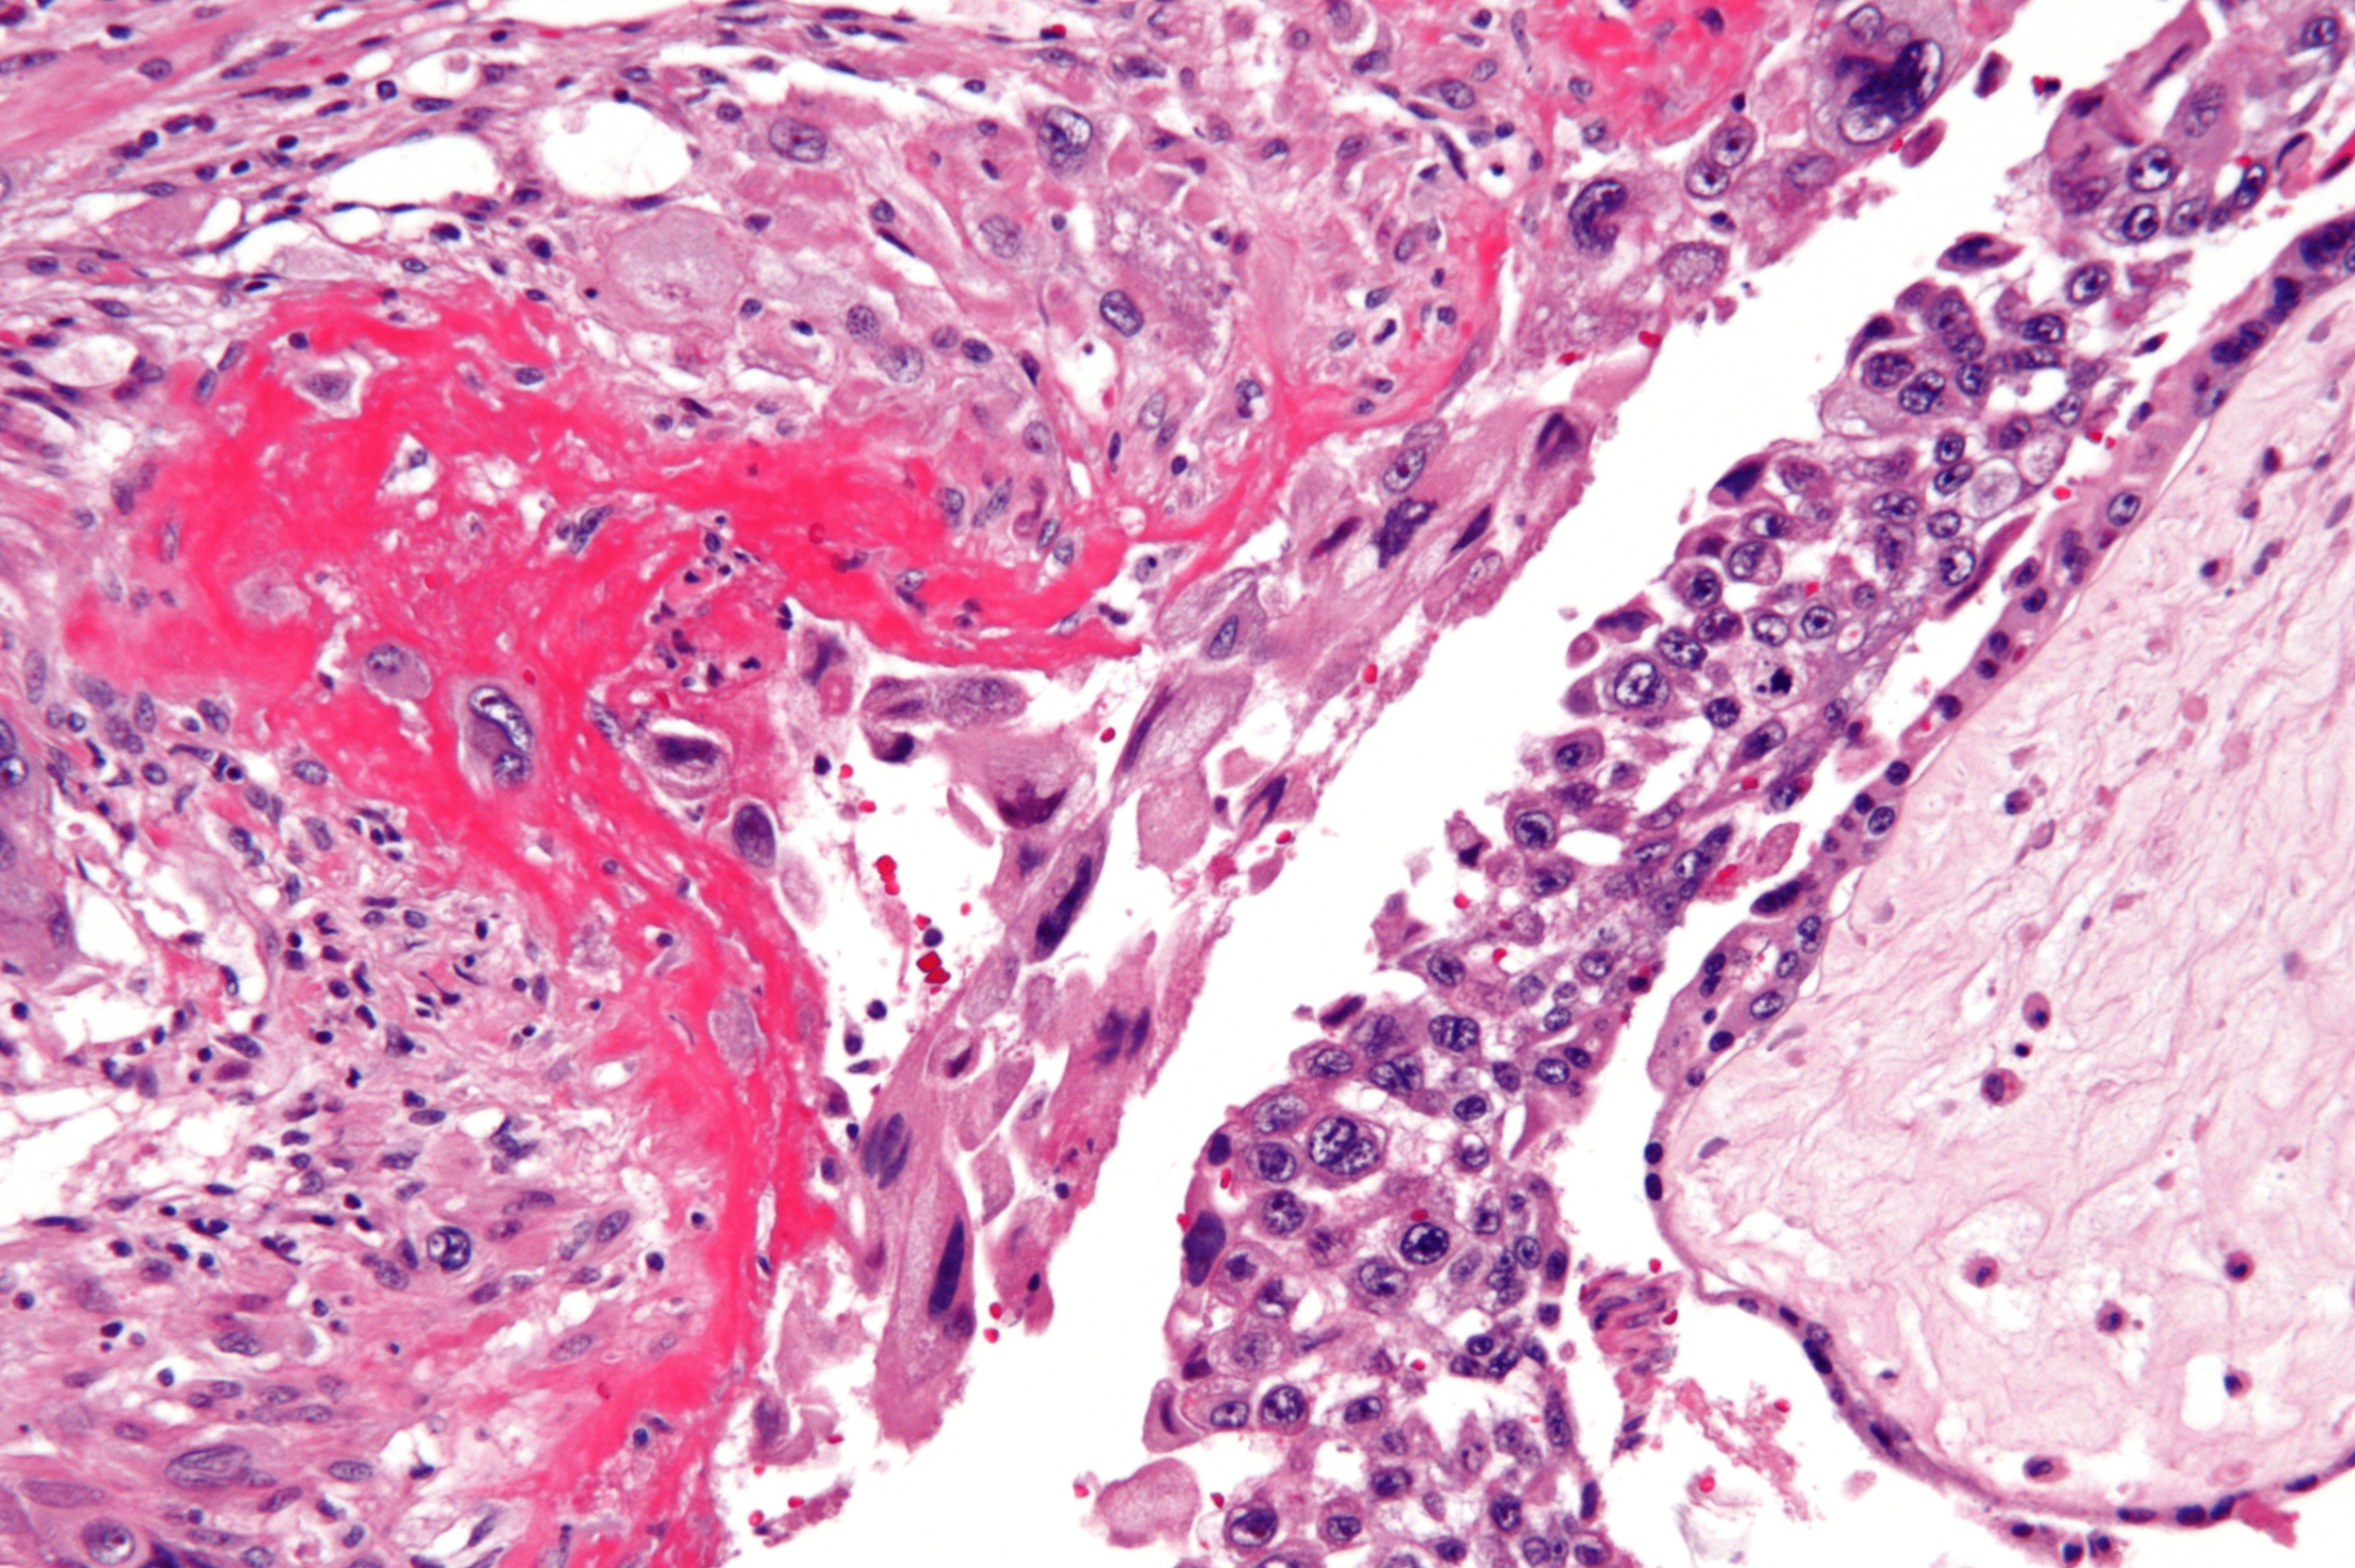

Partial hydatidiform mole, Wikimedia Commons

• 조직학적 형태:

- 일부는 정상, 일부는 낭포성 변화가 있는 융모

- 태아 구조가 일부 존재함

• 침윤이나 융모막암으로 진행한느 경우는 드묾

• hCG 수치는 증가하지만 완전 포기만큼 높지 않음